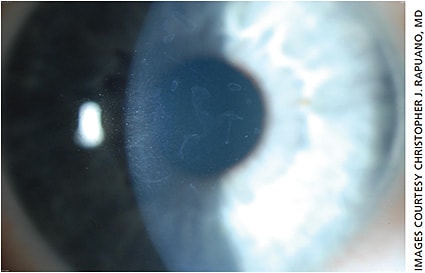

The best way to diagnose these conditions is a careful slit lamp examination. A broad slit beam from a side angle can often identify mild epithelial irregularities due to EBMD (Figure 1). It can also be used to find mildly elevated creamy white nodules of SND (Figure 2). A pterygium is not hard to diagnose on slit lamp examination. The question for all three of these conditions is whether they are visually significant and whether they require treatment prior to cataract surgery. Several diagnostic tests can help provide the answer.

SND involves single or multiple slightly or severely elevated creamy white corneal opacities. Usually these are located in the peripheral cornea, although they can involve the central cornea (Figures 6A and 6B, page 22). Even when peripheral, outside the central 6-mm zone, they can affect the central corneal topography and thereby the vision. While negative staining can be seen, many eyes with SND have significant irregular astigmatism noted on corneal topography.